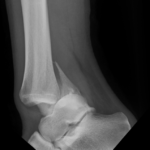

- Ankle Fractures.